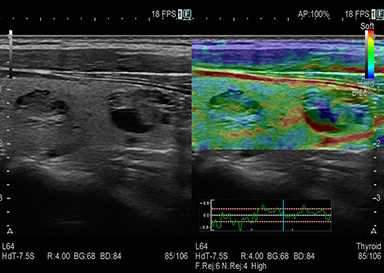

肝硬度・線維化・脂肪化測定

Shear Wave Measurement(SWM) / Attenuation計測(ATT)

組織にせん断波を発生させ、伝搬速度(Vs)を計測することで硬さを定量的に評価できます。肝脂肪化の程度を推定するための指標(ATT)も同時に計測します。

慢性肝障害のある方・脂肪肝がある方